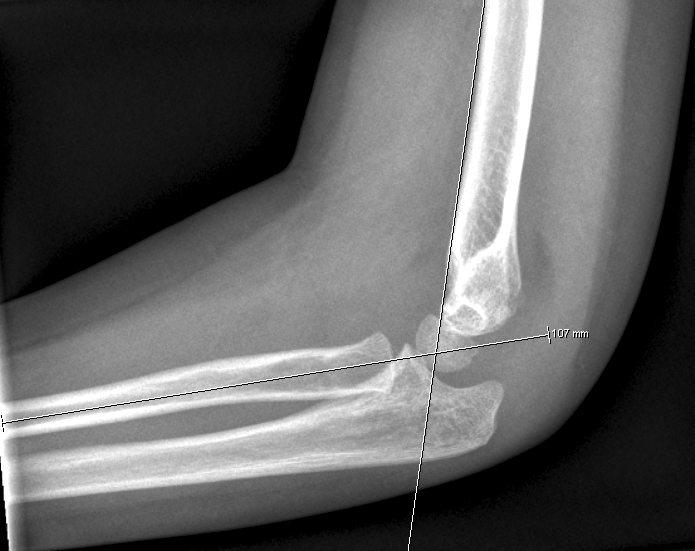

Dislokation: En linie langs forsiden af humerus går normalt igennem midterste

1/3 del af capitulum humeri. Hvis hele capitulum ligger bagved denne linje skal

der reponeres og osteosynteres i GA. Hos børn under 4 år tillades lidt større

Husk at vurdere at caput radii er på plads, ved at

kontrollere at en linje gennem radius går gennem centrum af capitulum humeri: